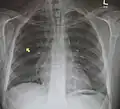

Pneumomediastinum is uncommon and occurs when air leaks into the mediastinum. The diagnosis can be confirmed via chest X-ray showing a radiolucent outline around the heart and mediastinum or via CT scanning of the thorax.